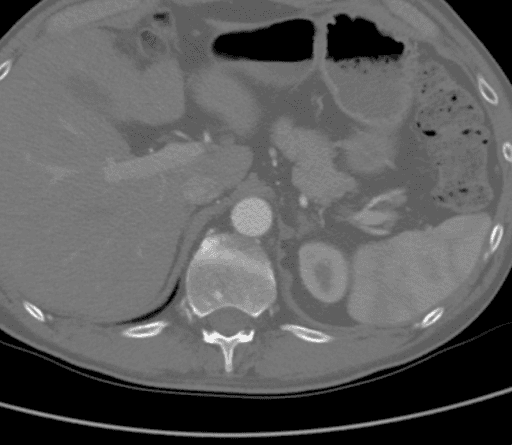

La CTA ha dimostrato un'occlusione aortica completa a livello delle arterie renali bilaterali da una combinazione di placca aterosclerotica calcificata e morbida. In modo significativo, in questo caso, l'ateroma si estendeva prossimalmente fino al livello dell'arteria mesenterica superiore (SMA), come visto nella Figura 1, il che avrebbe complicato il clamping suprarenale e compromesso l'afflusso appropriato per il bypass aortofemorale standard (AFB). L'aorta supraceliaca era priva di malattie arteriose (Figura 2). L'occlusione si estese alle arterie femorali comuni bilaterali, dove il flusso veniva ricostituito dalle arterie collaterali epigastriche e circonflesse iliache. Le arterie femorali comuni bilaterali (CFA) presentavano una placca ateromatosa di circa il 60% di stenosi, e poi il deflusso era intatto sotto la biforcazione della CFA.

Figura 1. La CTA ha mostrato che l'ateroma si estendeva prossimalmente fino al livello dell'arteria mesenterica superiore (SMA), il che avrebbe complicato il clamping suprarenale e compromesso l'afflusso appropriato per la AFB standard.